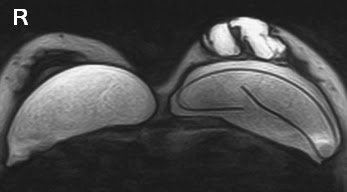

Breast implant ruptured